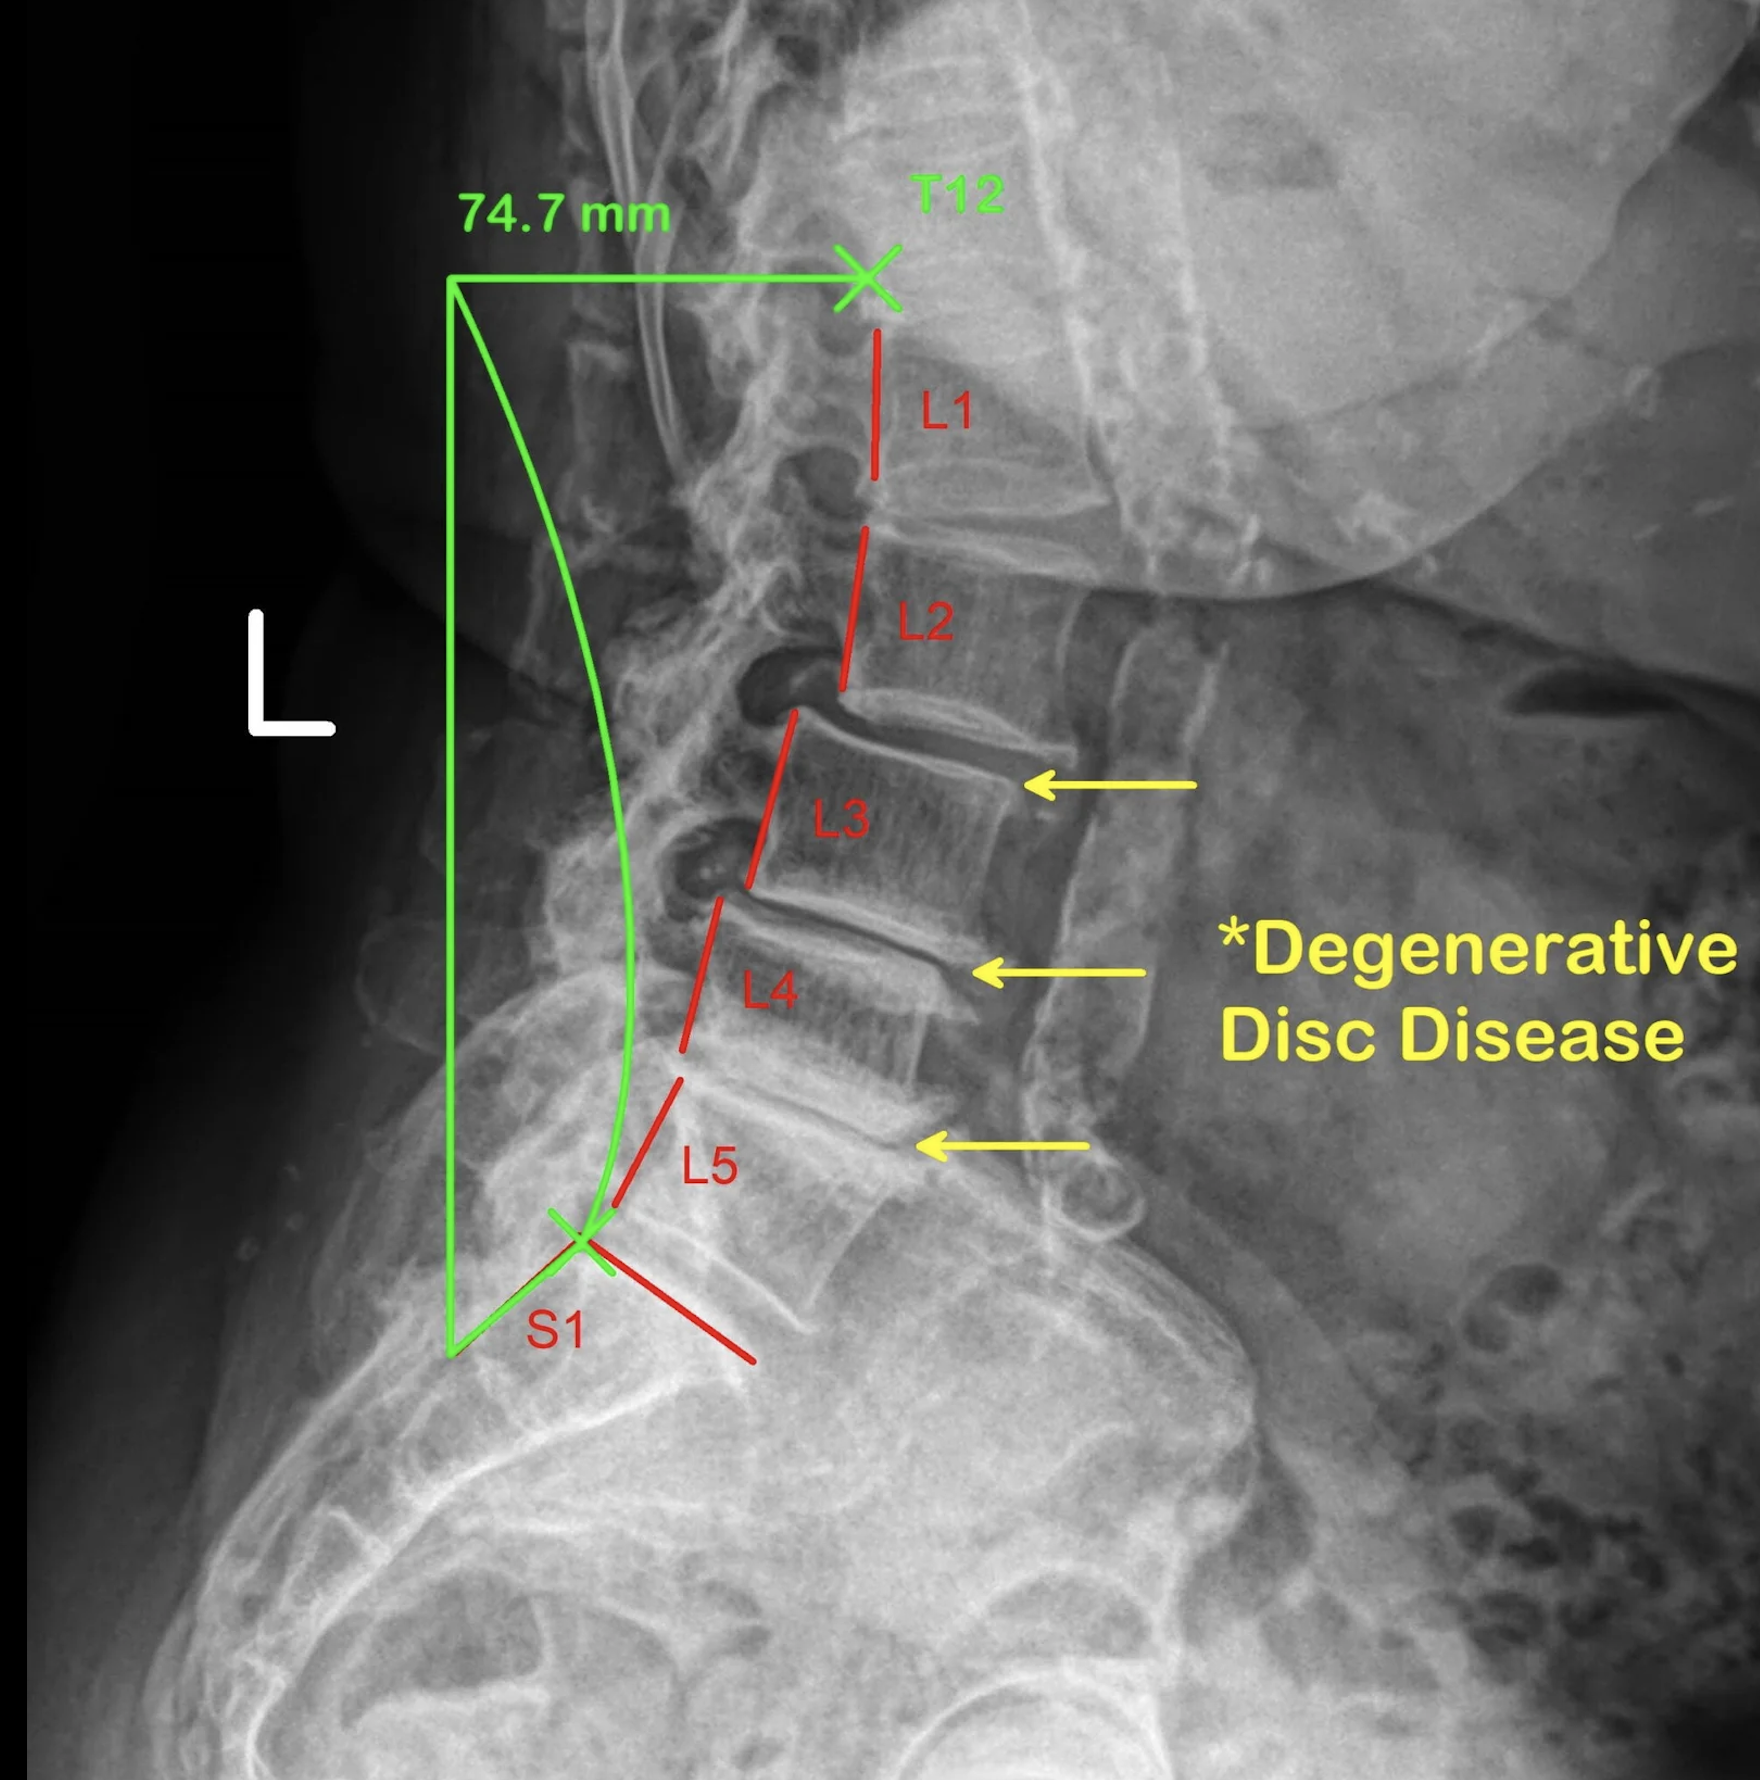

Degenerative Disc Disease (DDD)

Spine: Chronic Back Pain, Degenerative Disc Disease

• MRI findings and structural degeneration poorly correlate with pain; exercise targeting neuromuscular control and stability is the mainstay, not surgery.​